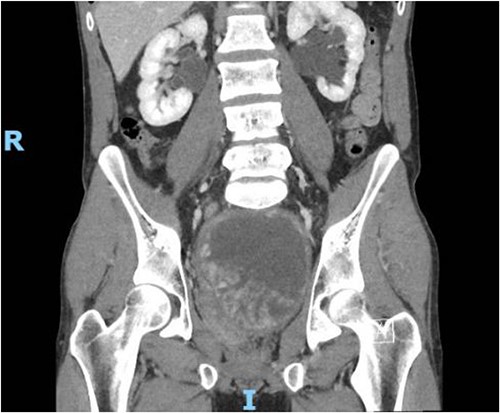

The patient presented to the ED 3 months later with urinary retention and pain; this was relieved with catheterization. A CT scan revealed that his tumor had slightly increased in size (Fig. 1). He had an AUA symptom index of 35. Due to the refractory nature of his obstructive symptoms, he was scheduled for a TURP 2 weeks later, which again revealed leiomyoma. He was kept on interval follow-up for the next 2 years. During that time his PSA was 1.13 ng/ml. Magnetic resonance imaging (MRI) pelvis 2 years later showed the mass appeared to communicate with the posterior bladder neck (Fig. 2). His baseline renal function kept worsening (Creatinine 1.4 mg/dl); at that time, the patient was counseled regarding his treatment options, and he opted for surgery which he was told may require the removal of the prostate with loss of ejaculatory and/or erectile function.

Contrast CT pelvis (May 2020) showing stable complex solid and cystic pelvic mass abutting displacing the bladder superiorly and the prostate laterally.